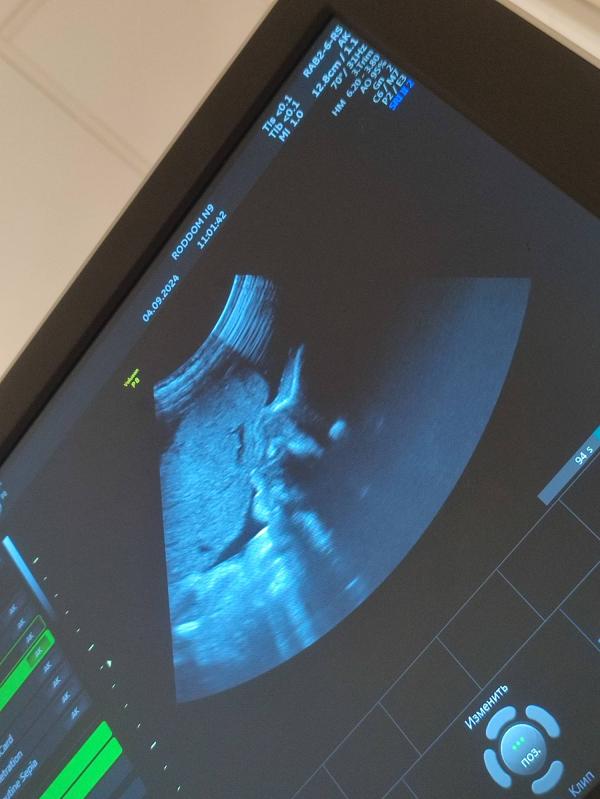

Поднялась я на дневной стационар посмотрели направление, отправили вниз в роддом (где приёмный покой) на узи + сдать мочу и сказали, что если белок будет 0.3, то они меня возьмут, если больше 0.3, то в стационар лягу. Спустилась долго сидела в очереди на узи (девушек было много) в итоге подошла моя очередь посмотрели малыша у него всё хорошо, кровотоки хорошие, весит он 1 кг 826 грамм, лежит в головном предлежании, пинается в правый бок ногами. Почки тоже хорошие, правая увеличина, но мне сказали, что это пройдёт после родов.